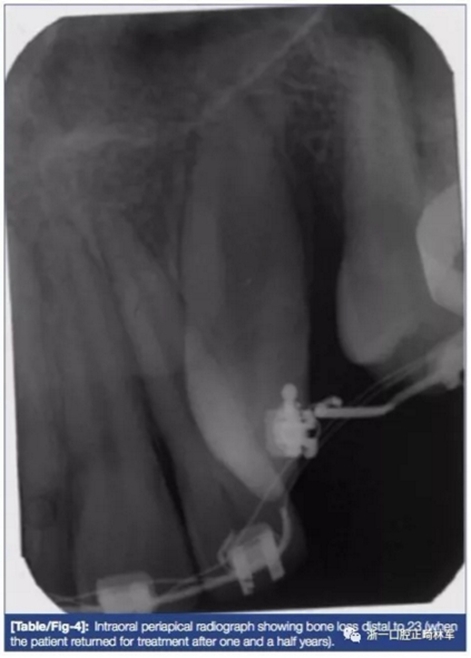

4月后,13排入弓形,23牙冠從腭側(cè)形90°近中旋轉(zhuǎn)萌出?;颊哂捎趥€(gè)人原因,于一年半后復(fù)診。

修改后治療計(jì)劃:

拍攝X片后提示23遠(yuǎn)中較大骨缺損(圖4)。為加快時(shí)間同時(shí)增加骨量,計(jì)劃形PAOO手術(shù)并植入干燥骨粉(FBDA)(圖5)。術(shù)后予3天500mg阿莫西林及1日止痛藥(500mg對(duì)乙酰氨基酚每日兩次)。